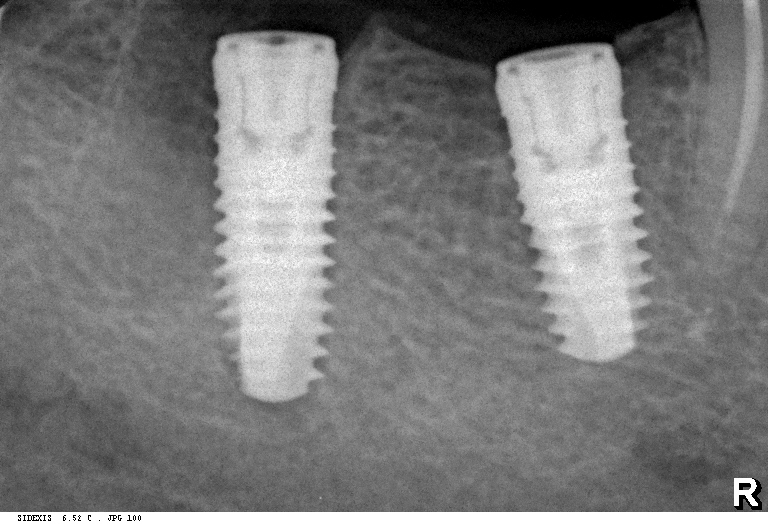

В 2025 году мы внедрили две новые для себя имплантационные системы компании Dentsply Sirona Implants: Astra Tech EV и PrimeTaper EV. В сравнении с уже имеющимися, эти системы уже адаптированы к т. н. «цифровому протоколу», имеют все необходимые компоненты для работы по современным методикам протезирования.

Мы работаем с новыми имплантами уже полгода, накопили приличный опыт их использования, дотошно их изучили и уверенно можем утверждать, что получили в свои руки мощный инструмент стоматологической реабилитации. Поэтому в следующем году тебя ждет не одна и не две публикации о новых имплантационных системах Dentsply Sirona Implants. Они появятся сразу, как мы получим внятные долгосрочные результаты их применения.